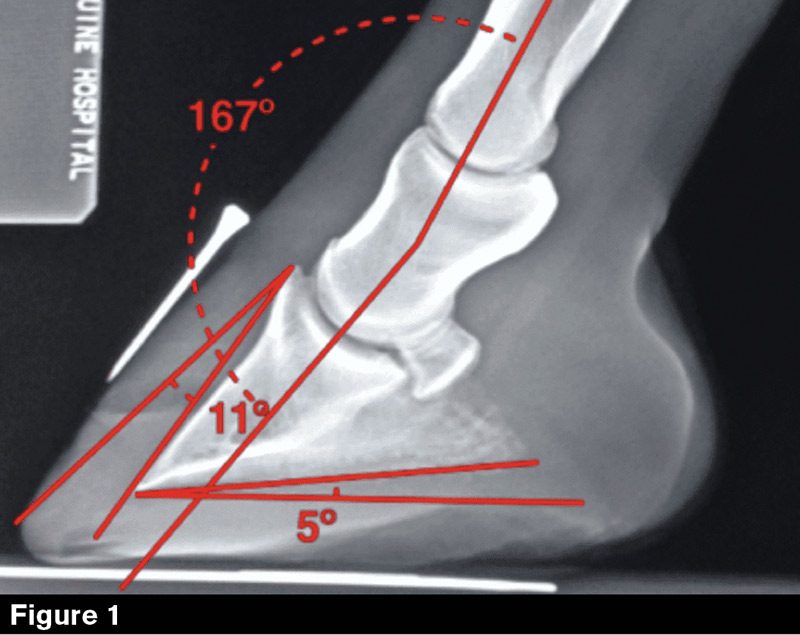

It wasn’t until digital radiographs came out that we started getting radiographs with all kinds of letters, angles, arrows and points (Figure 1 above). They helped us a lot because they’re clear, but I’m going to get into how we have to be cautious with radiographs.